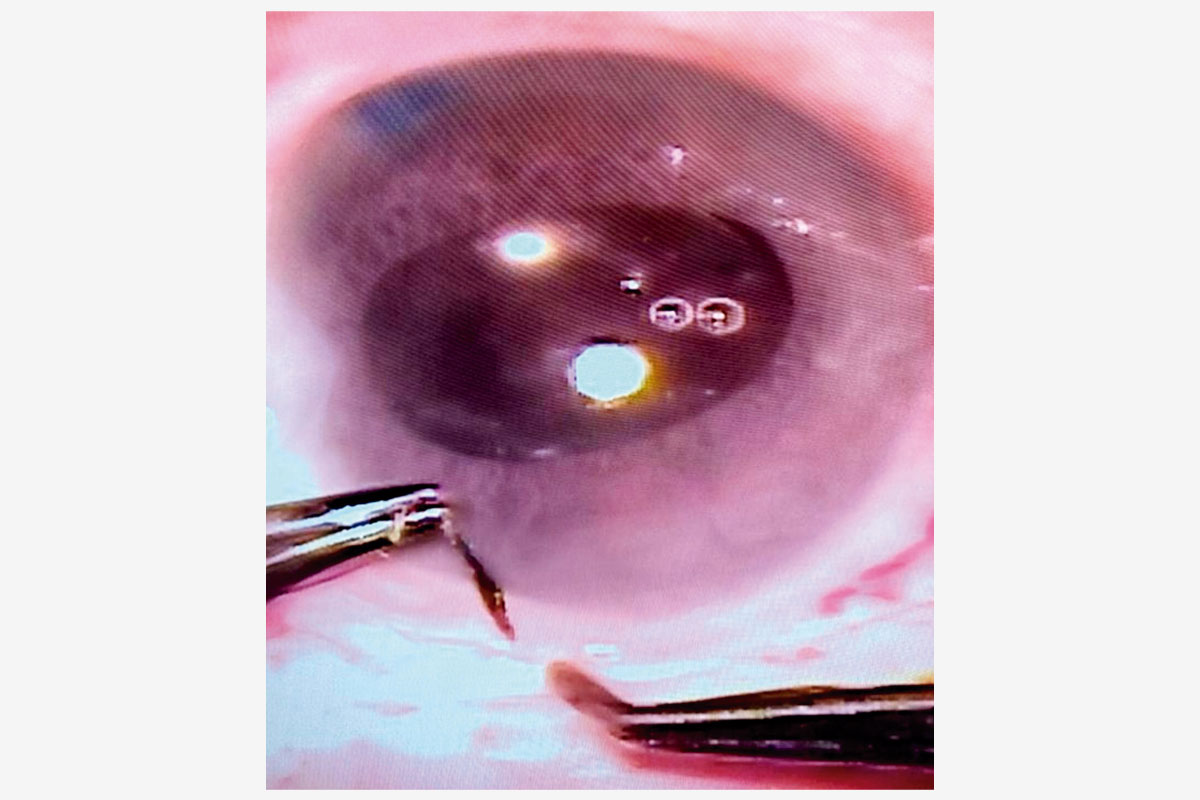

Ante este escenario, donde la dureza nuclear y la estrechez del espacio de maniobra hacían de la facoemulsificación una opción de alto riesgo para el endotelio, se optó por una MSICS con abordaje temporal para minimizar el riesgo endotelial y proteger la ampolla filtrante superior. Se confeccionó un túnel escleral de 7 mm para una extracción del núcleo sin estrés mecánico (Figura 5). Se implantó una lente intraocular de tres piezas bajo viscoelástico y se aseguró la hermeticidad con un único punto corneoescleral (Figura 6).

Figura 5. Túnel escleral de la MSICS